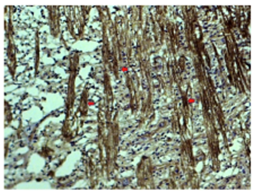

Figure 4 Case#3 OS: Photomicrograph from temporal lamina cribrosa demonstrating what we interpret as multiple early forms of evolving endbulb swellings (3 red arrows) among many more in individual axons within mid-laminar axon bundles which suggest axonal injury possibly secondary to transient elevation of IOP before death. (APP-A4 Hematoxylin and bluing; original magnification X 31.25).

We obtained heavy APP-A4 staining in RGCs from the 40year-old Case #1 demonstrating potential for remarkable stability and durability of the protein components in formalin-fixed paraffinized tissues (Figure 1). Obviously one such demonstration does not establish that any similarly agedor older paraffin material will reliably work with this marker. However this one example is a good reason to further explore the use of this APP-A4 marker in long-stored paraffin embedded human ocular tissue if results might be pertinent to ongoing human autopsy studies. Our larger series of cases will include several in which paraffin embedding dates back to 2010, allowing better estimation of the marker’s durability in general over at least 10years. Case #2 demonstrated an optic nerve infarct beginning approximately 6mm posterior to the globe, expanding to involve nearly the whole diameter of the nerve in deeper sections from the most posterior portion, some 29mm behind the globe likely into the chiasm since the orbital and optic canal portions of the nerve together average approximately 29mm in length (Figure 2). In this example, APP-A4 intra-axonal accumulations were found clearly outlining the anterior end of the infarct in agreement with routine Hematoxylin and Eosin (H&E) and Periodic Acid-Schiff(PAS) stains (Figure 2A-D). While not surprising this does illustrate how blocked orthograde axonal transport is sharply interrupted by an adjacent infarction. Case #3 illustrates for the first time both orthograde and retrograde axonal transport block corresponding to anterior and posterior sides of a hemorrhagic optic nerve contusion (Figure 3A-C & Figure 4). Case #4, to our knowledge is the best demonstration ever illustrated demonstrating bilaterally symmetrical APP-A4 macular input and classic end-bulb swellings in the lamina cribrosa OU, in our view reinforcing no need for non-AHT controls (Figure 5).8,9 The symmetry of APP-A4 staining of RGCs and optic nerve heads with laminar end-bulb swellings in axons across companion eyes in this case well document expected vigorous bilateral pre-mortem orthograde axonal transport physiology at least to the lamina cribrosa.